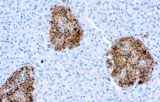

CE/IVD antibodies for immunohistochemistry (IHC) in neuropathology are validated in vitro diagnostic reagents used to detect specific neuronal and glial antigens in formalin-fixed paraffin-embedded (FFPE) tissue. Peer-reviewed neuropathology literature supports their role in improving reproducibility and diagnostic accuracy in central nervous system (CNS) diseases, including brain tumors and neurodegenerative disorders.

Targeted proteins such as GFAP, OLIG2, NeuN, synaptophysin, neurofilament, and Iba1 reflect astrocytic, oligodendroglial, neuronal, and microglial lineages. Their expression patterns are widely used in peer-reviewed studies to define CNS cell identity, differentiation state, and neuroinflammatory or degenerative processes.

CE/IVD IHC antibodies support CNS tumor classification (gliomas, embryonal tumors, metastases), assist in differential diagnosis, and help identify proteinopathies associated with Alzheimer’s disease and other neurodegenerative conditions. They are routinely used in biomarker panels for tumor grading and diagnostic stratification in neuro-oncology.